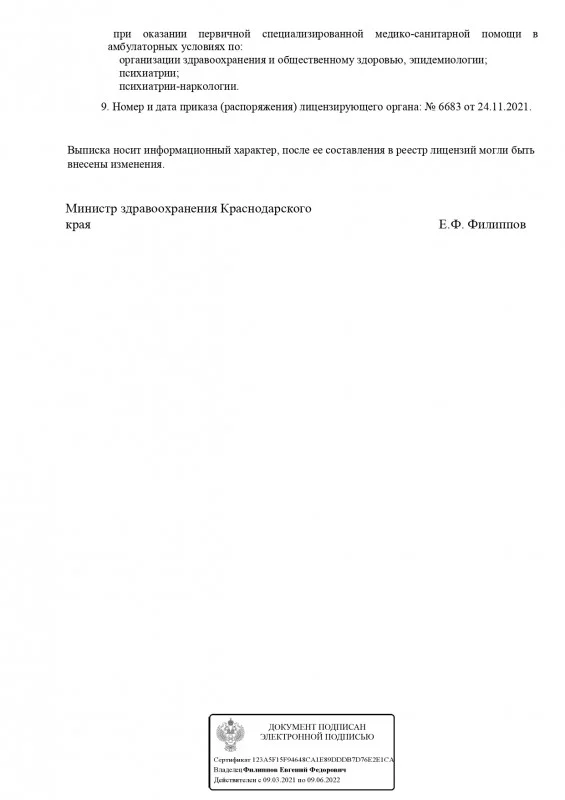

Лицензия на осуществление медицинской деятельности

Лицензия на осуществление медицинской деятельности

Лицензия на осуществление медицинской деятельности

Лицензия на осуществление медицинской деятельности

Лицензия на осуществление медицинской деятельности

Лицензия на осуществление медицинской деятельности

Лицензия на осуществление медицинской деятельности

Лицензия на осуществление медицинской деятельности